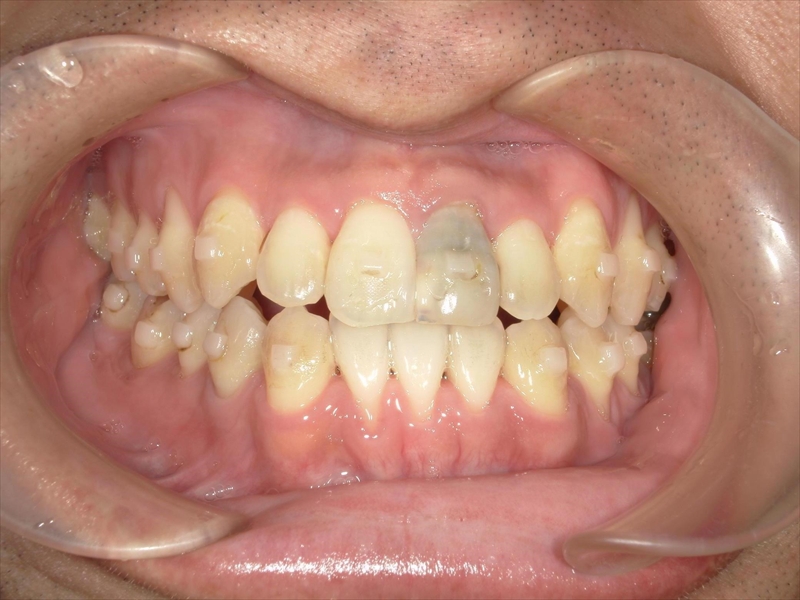

この症例は、20代男性の大人の矯正治療です。

上の歯は歯が並ぶスペースが足りず、八重歯を含むガタガタした歯並びになっていました。

下の歯は、受け口気味で、さらに右下の前から2番目の歯が1本足りない状態でした。

また、歯並び全体がお顔の中心よりも右にずれており、噛み合わせも左右で違っていました。

右側では下の歯が前に出すぎており、左側では逆に下の歯が少し後ろに下がっているという、左右でバランスの取れていない噛み合わせでした。

治療前後 写真